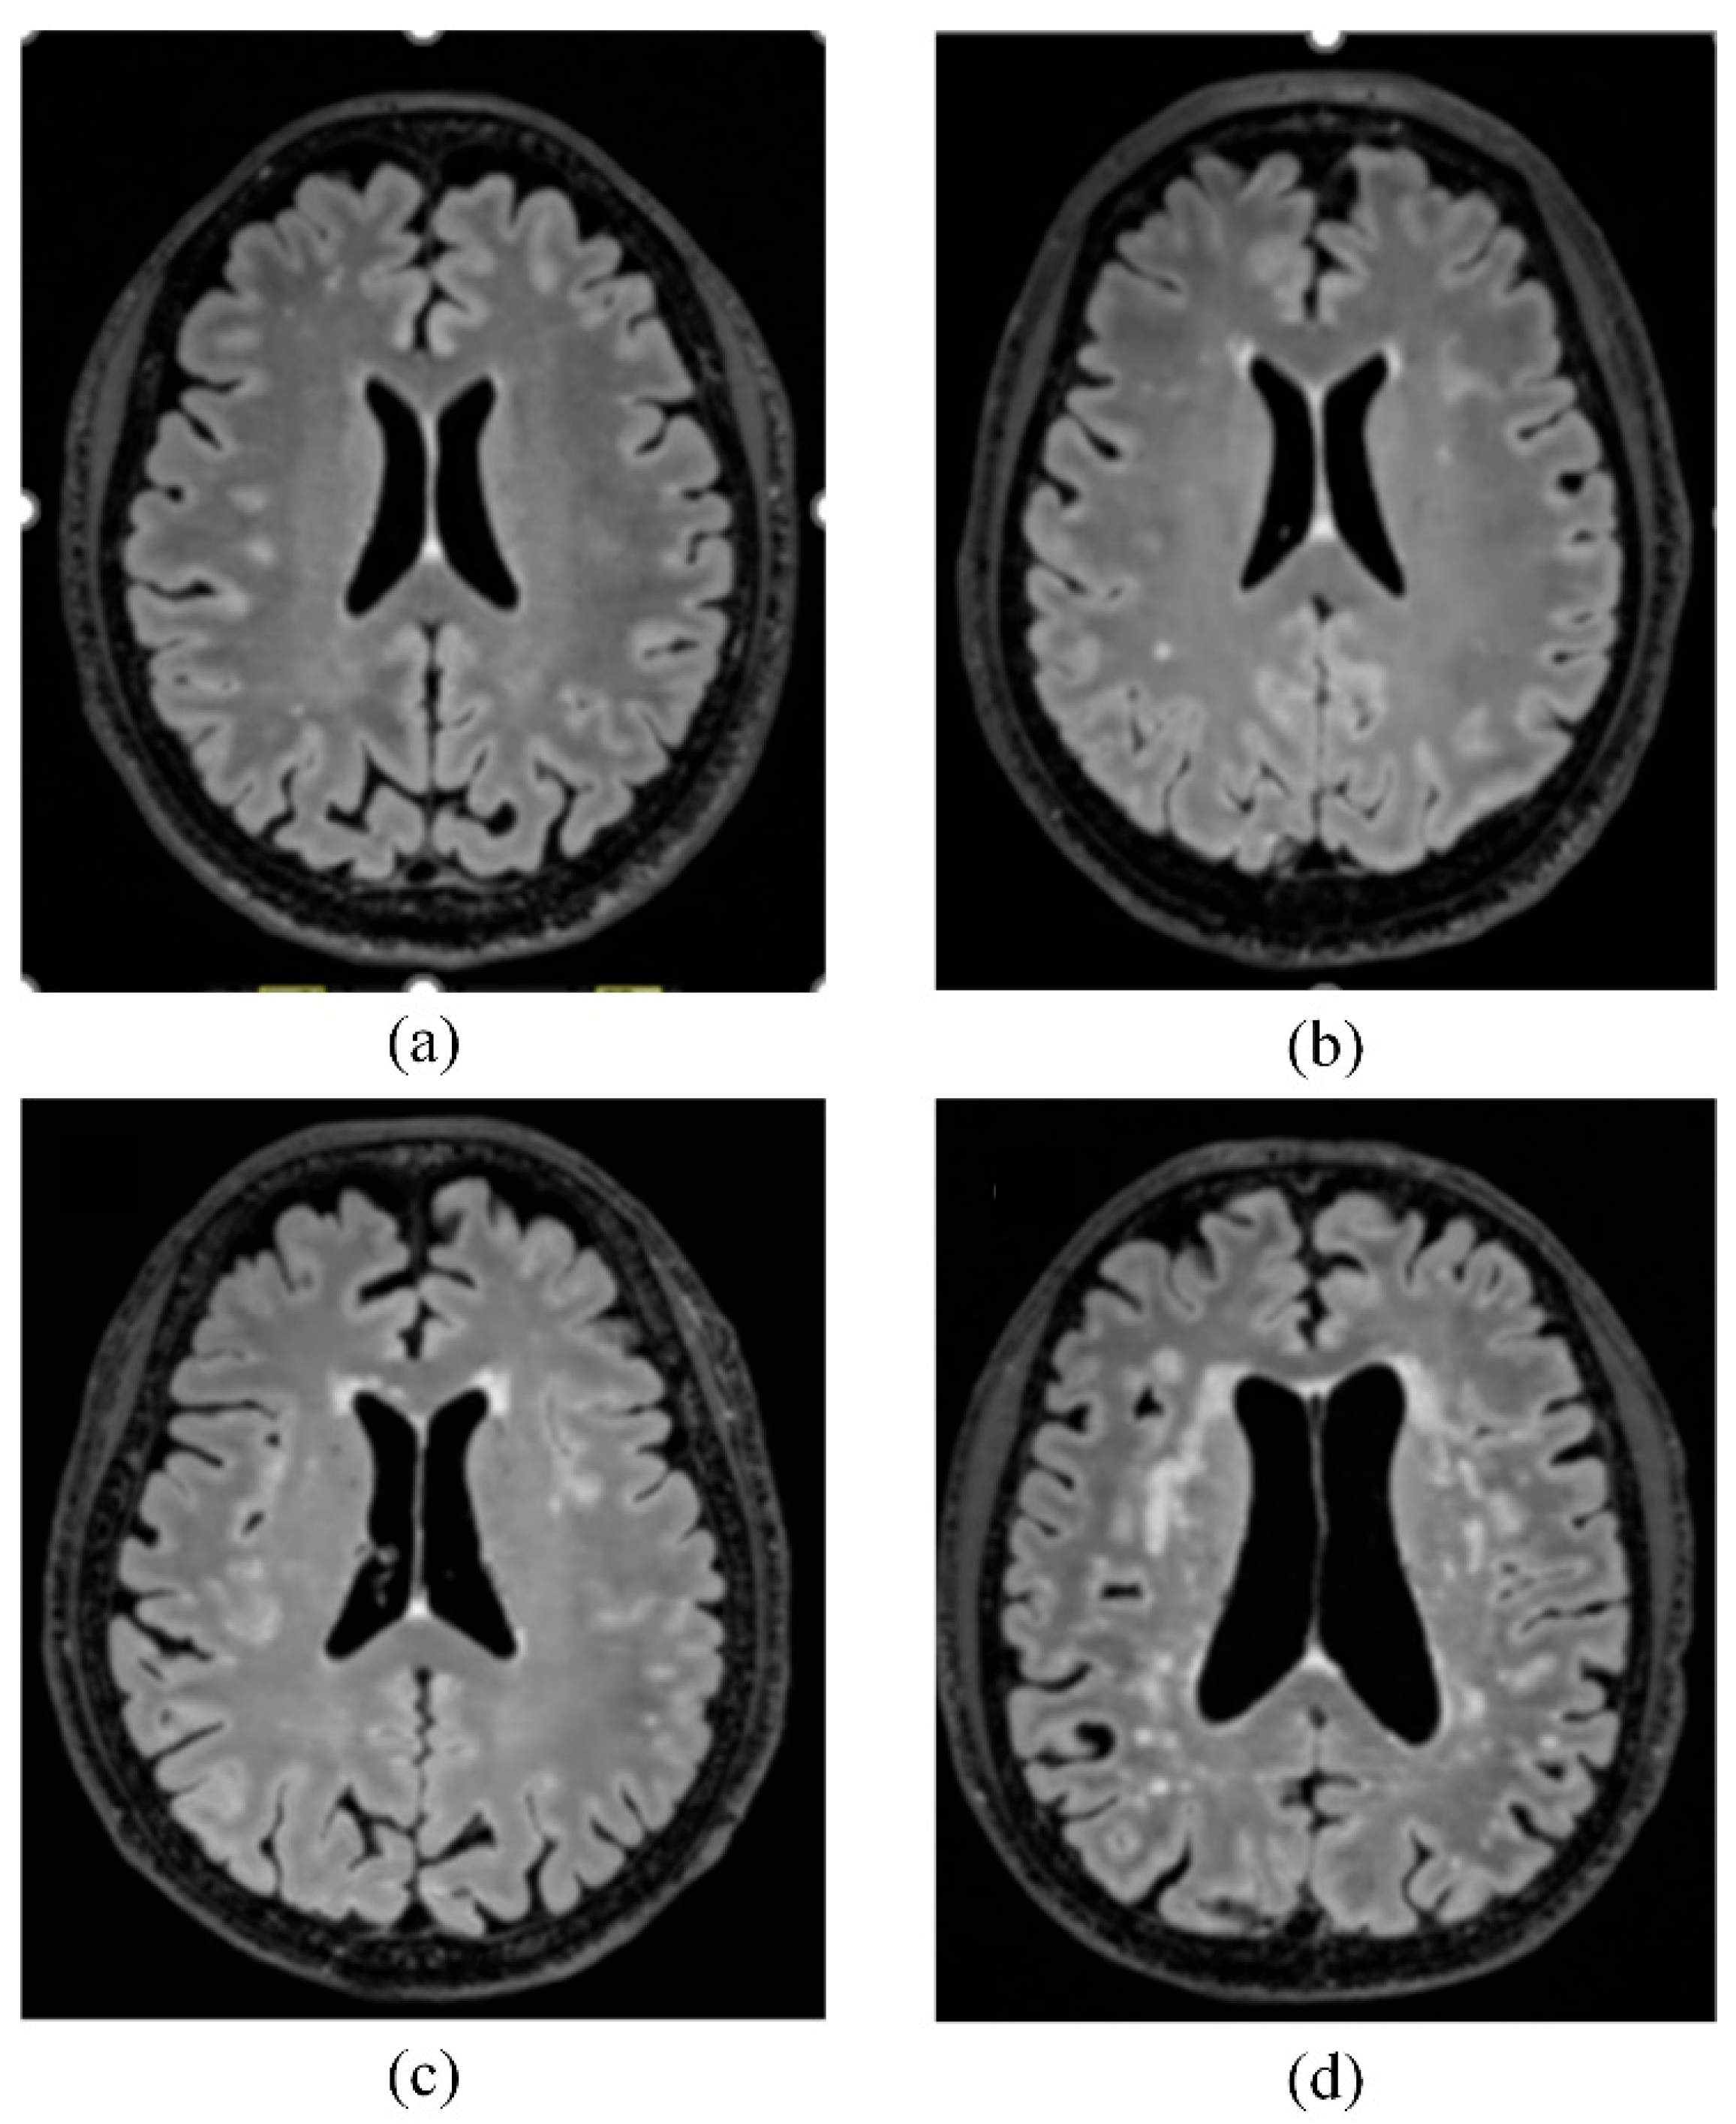

- Fazekas, F.; Kleinert, R.; Offenbacher, H.; Schmidt, R.; Kleinert, G.; Payer, F.; Radner, H.; Lechner, H. Pathologic correlates of incidental MRI white matter signal hyperintensities. Neurology 1993, 43, 1683–1689. [Google Scholar] [CrossRef]

- Joo, L.; Shim, W.H.; Suh, C.H.; Lim, S.J.; Heo, H.; Kim, W.S.; Hong, E.; Lee, D.; Sung, J.; Lim, J.S.; et al. Diagnostic performance of deep learning-based automatic white matter hyperintensity segmentation for classification of the Fazekas scale and differentiation of subcortical vascular dementia. PLoS ONE 2022, 17, e0274562. [Google Scholar] [CrossRef] [PubMed]